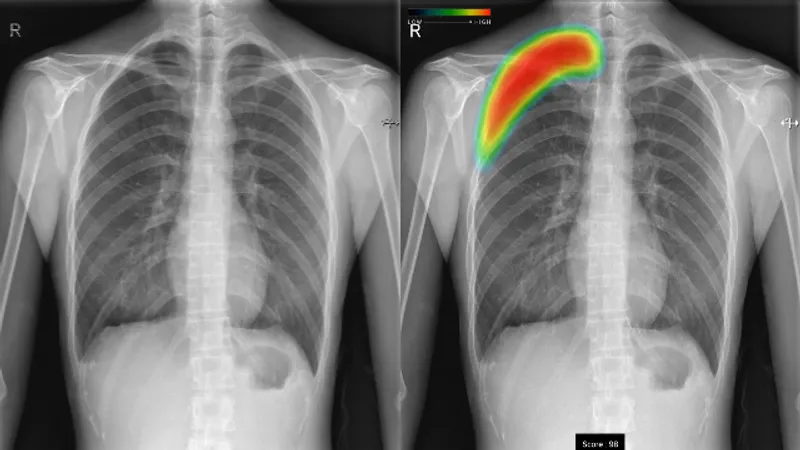

(1)ヒートマップ表示、スコア表示機能 結節・腫瘤影、浸潤影、気胸の候補領域を検出し、それらの異常領域の存在の可能性(確信度)を青から赤までのグラデーションカラーで表示します。確信度が低いほど青く、高いほど赤く表示します。また、各検出領域に対応する確信度の最大値をスコアで表示します。 (2)3つの画像所見に対応 本ソフトウェアの検出対象は、主要な肺疾患の画像所見である結節・腫瘤影、浸潤影、気胸の3所見です。健康診断や日常診療などにおけるさまざまな胸部疾患の診療に幅広く活用いただけます。